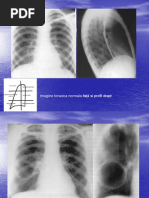

- prin calcul: CPT = CV + VR sau CPT = CI + CRF ; - prin metoda dilutiei He prin respiratie unica in circuit deschis - prin metoda radiologica: masurarea CPT pe radiografii toracopulmonare, efectuate in proiectii postero- anterioara si laterala, cu subiectul in apnee dupa un inspir maximal, eventual prelucrarea computerizata a rezultatului.

Curba flux volum in timpul unui Inspir si expir normal si in unul fortat la un pacient sanatos